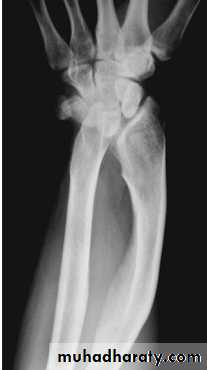

Madelung deformity

Forward curvature of the lower radius and backward subluxation of the lower ulna.Cause: congenital or post-traumatic.

If symptomatic treated by radial osteotomy.